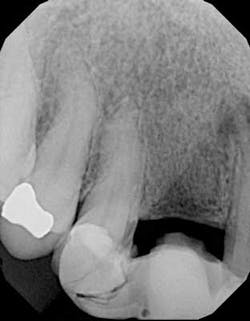

Immediately post-insertion, a periapical radiolucency was detected on the post-insertion radiograph on tooth No. 7 and the patient was immediately sent for root canal therapy. Four months was allowed for implant integration. At the time of Stage II, a noninvasive punch tissue technique was employed and a 3 mm healing abutment was placed. At the time of impression, an open tray technique was used and a custom abutment was selected. Because of the patient’s canine guidance occlusion, a porcelain-fused-to-metal crown was selected along with all-ceramic crowns on teeth Nos. 5 and 7.

One year post-insertion radiographs indicate that bone levels around the implant remain stable. Clinical results 1.5 years post-insertion reveal gingival levels to be stable and healthy, and the patient is very pleased with the esthetic result of his treatment.